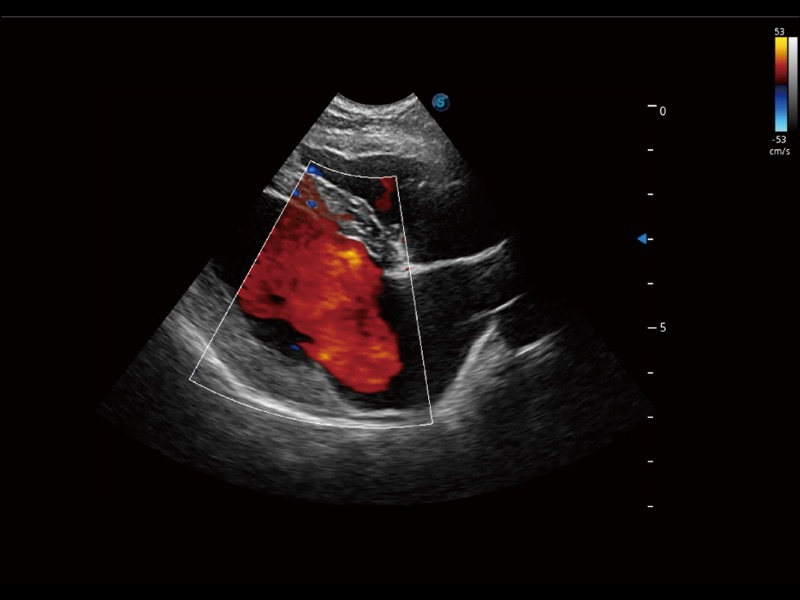

采用红、橙、黄、绿、青、蓝、紫这七种肉眼最为敏感的色彩,直观地显示组织内血流灌注的时间先后信息,更精准捕捉血流灌注走行细节。